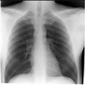

Temiz Akciğer Tomografisi Ne Anlama Geliyor?Günümüzde tıpta tanı ve tedavi süreçlerinde önemli bir yer tutan görüntüleme yöntemlerinden biri olan akciğer tomografisi, hastalıkların teşhisinde kritik bir rol oynamaktadır. "Temiz akciğer tomografisi" ifadesi, genellikle akciğerlerde herhangi bir anormal bulguya rastlanmadığı anlamına gelir. Bu bağlamda, temiz bir akciğer tomografisi sonucu, hastanın akciğer sağlığının iyi olduğunu gösterir. Akciğer Tomografisi Nedir?Akciğer tomografisi, yüksek çözünürlüklü görüntüler elde etmek için X-ray teknolojisini kullanan bir görüntüleme yöntemidir. Bu yöntem, akciğerlerin iç yapısının detaylı bir şekilde incelenmesine olanak tanır. Tomografi, akciğerlerdeki lezyonlar, tümörler, enfeksiyonlar ve diğer patolojilerin tespit edilmesinde son derece etkili bir yöntemdir. Temiz Akciğer Tomografisi SonucuTemiz bir akciğer tomografisi sonucu, şu durumları ifade edebilir: